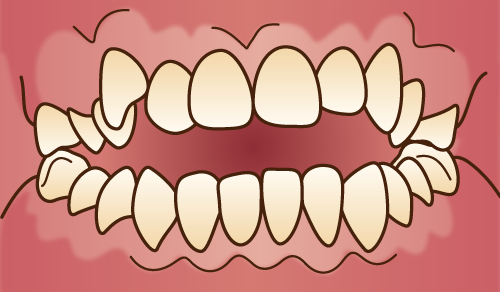

反対咬合(下顎前突)

下顎前突

下顎前歯が上顎前歯よりも、歯性、機能的、骨格的に前突し、正常咬合と逆になっている状態。

①上顎前歯が舌側傾斜もしくは転位している。

②臼歯部のう蝕による歯冠崩壊が著しい。

③下顎全体が近心転位している。

④上顎の発育不全がある。

①乳歯の萌出位置異常が原因になることがある。②臼歯部で咬めないなど、機能的に顎を前に出して前歯部で咬む癖がある人に多い。③遺伝的な場合がある。 ④口唇口蓋裂の人に多い。